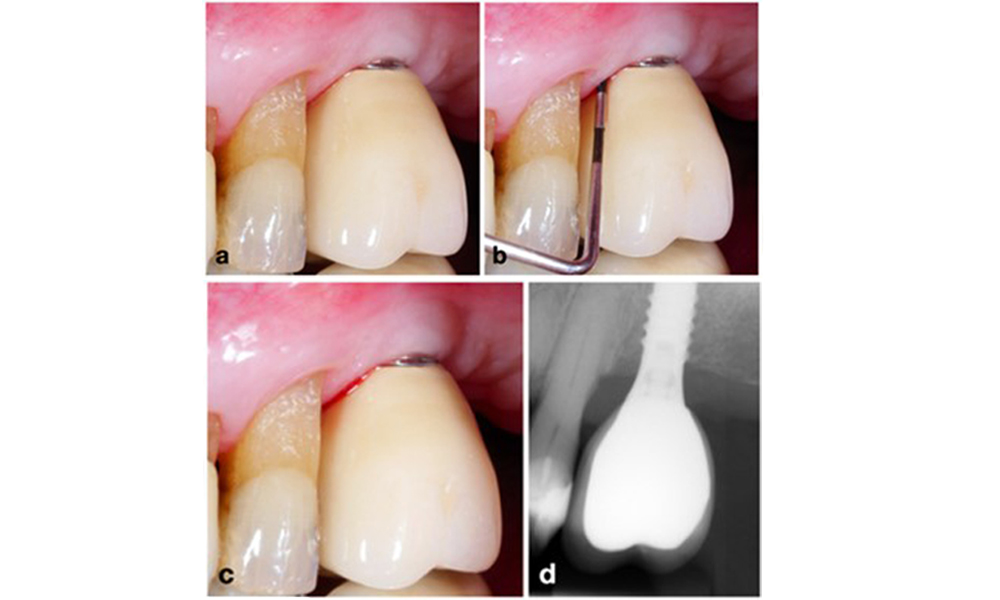

The World Workshop on the Classification of Periodontal and Peri‐Implant Diseases and Conditions from 2017 established diagnostic criteria for peri-implant mucositis and peri-implantitis (Renvert et al. 2018). Peri-implant mucositis is defined as (1) presence of inflammation around the implant (i.e., redness, swelling, line or drop of bleeding within 30 seconds of probing), combined with (2) no additional bone loss after initial healing (figure 1).